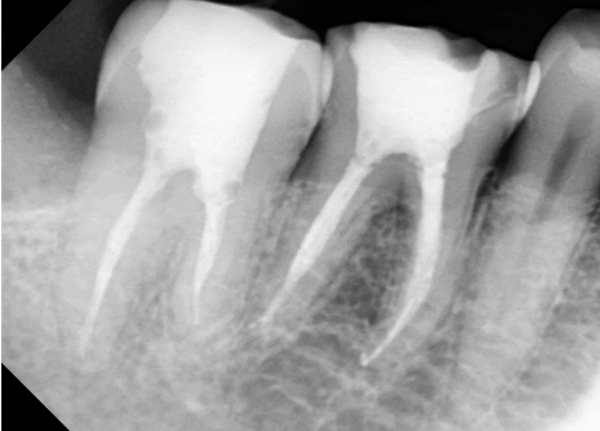

자연치아를 살리는 마지막 선택, 신경치료

The Last Choice to Save Natural Teeth, Neurotherapy

치아의 치수가 손상되었거나, 감염되었을 때 ‘신경치료’를 하게 됩니다.

가령 충격을 받아 파절이 일어나거나 광범위한 치아 우식증으로 인한 경우가 그렇습니다.

사람에게 단 하나뿐인 자연치아를 발치하는 것은 너무나 아까운 선택이기 때문에

그 자연치아를 발치하지 않고 보존하기 위해 시술됩니다.

신경치료에서 가장 중요한 부분 중 하나는 감염이 절대로 있어서는 안되는 것 입니다.

때문에 저희 더서울치과에서는 클램프와 러버댐을 이용하여 완벽한 방습환경을 갖추고

경험이 많은 보존과 전문의에 의해 치료를 해 드리고 있습니다.

충치로 인해 고생을 하고 계시다면 더서울치과에서 안전하고 꼼꼼한 진료를 받아보세요.

소중한 자연치아를 지켜주세요.